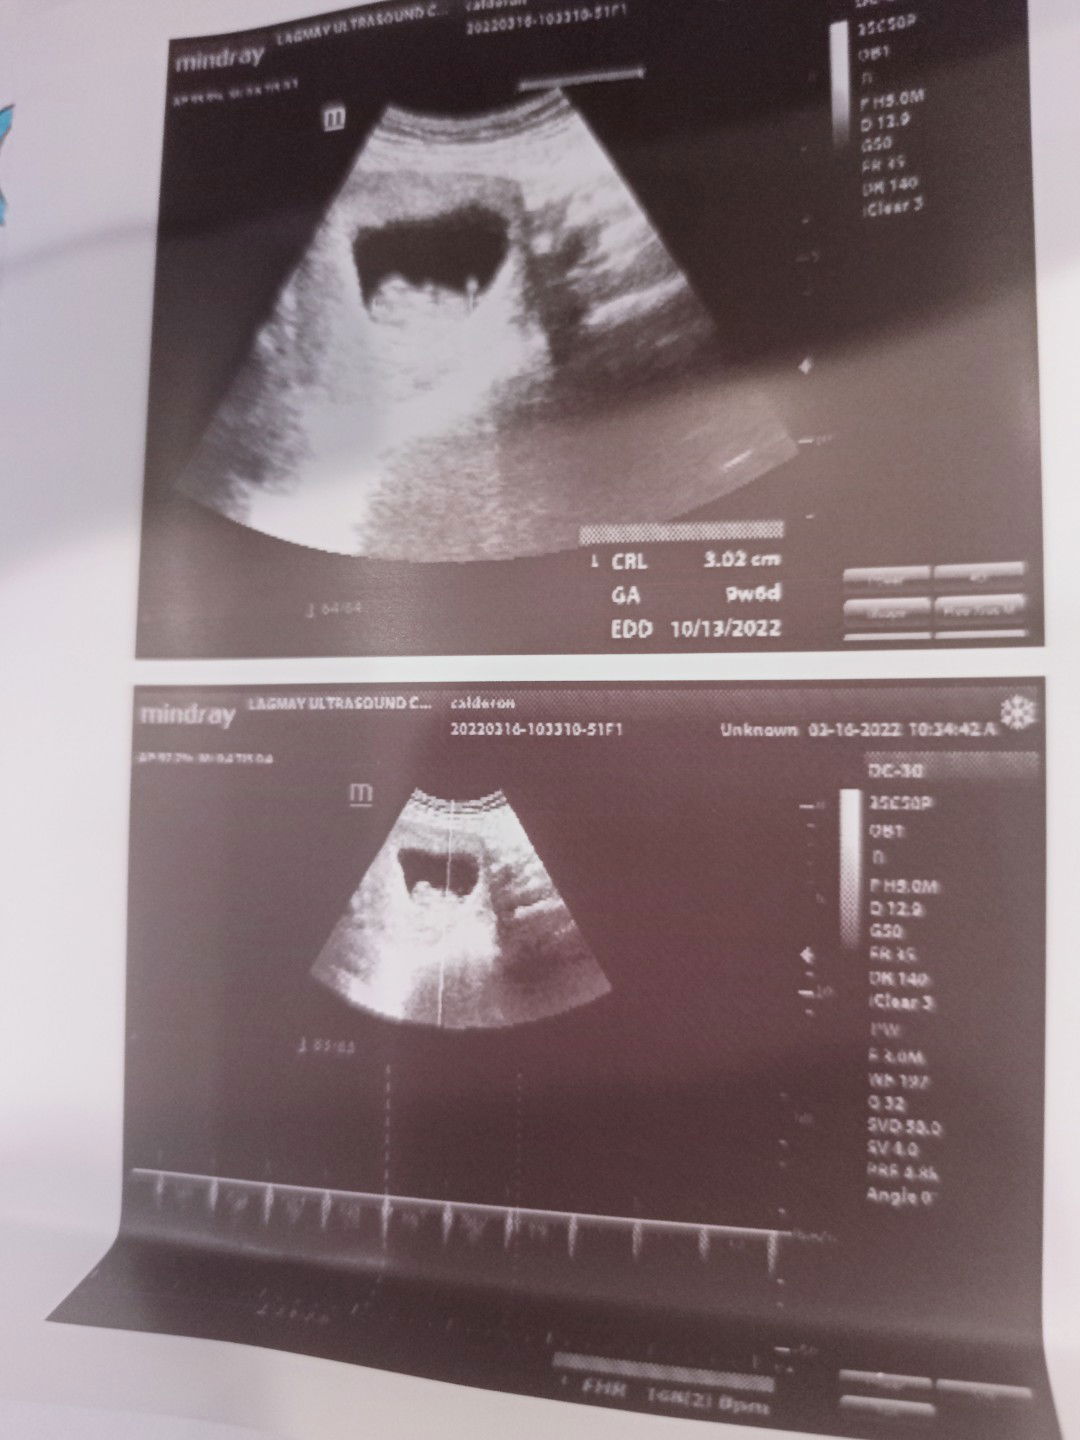

ito ang sign na magpa ultrasound ka 😂

18 to 20 weeks na para sure